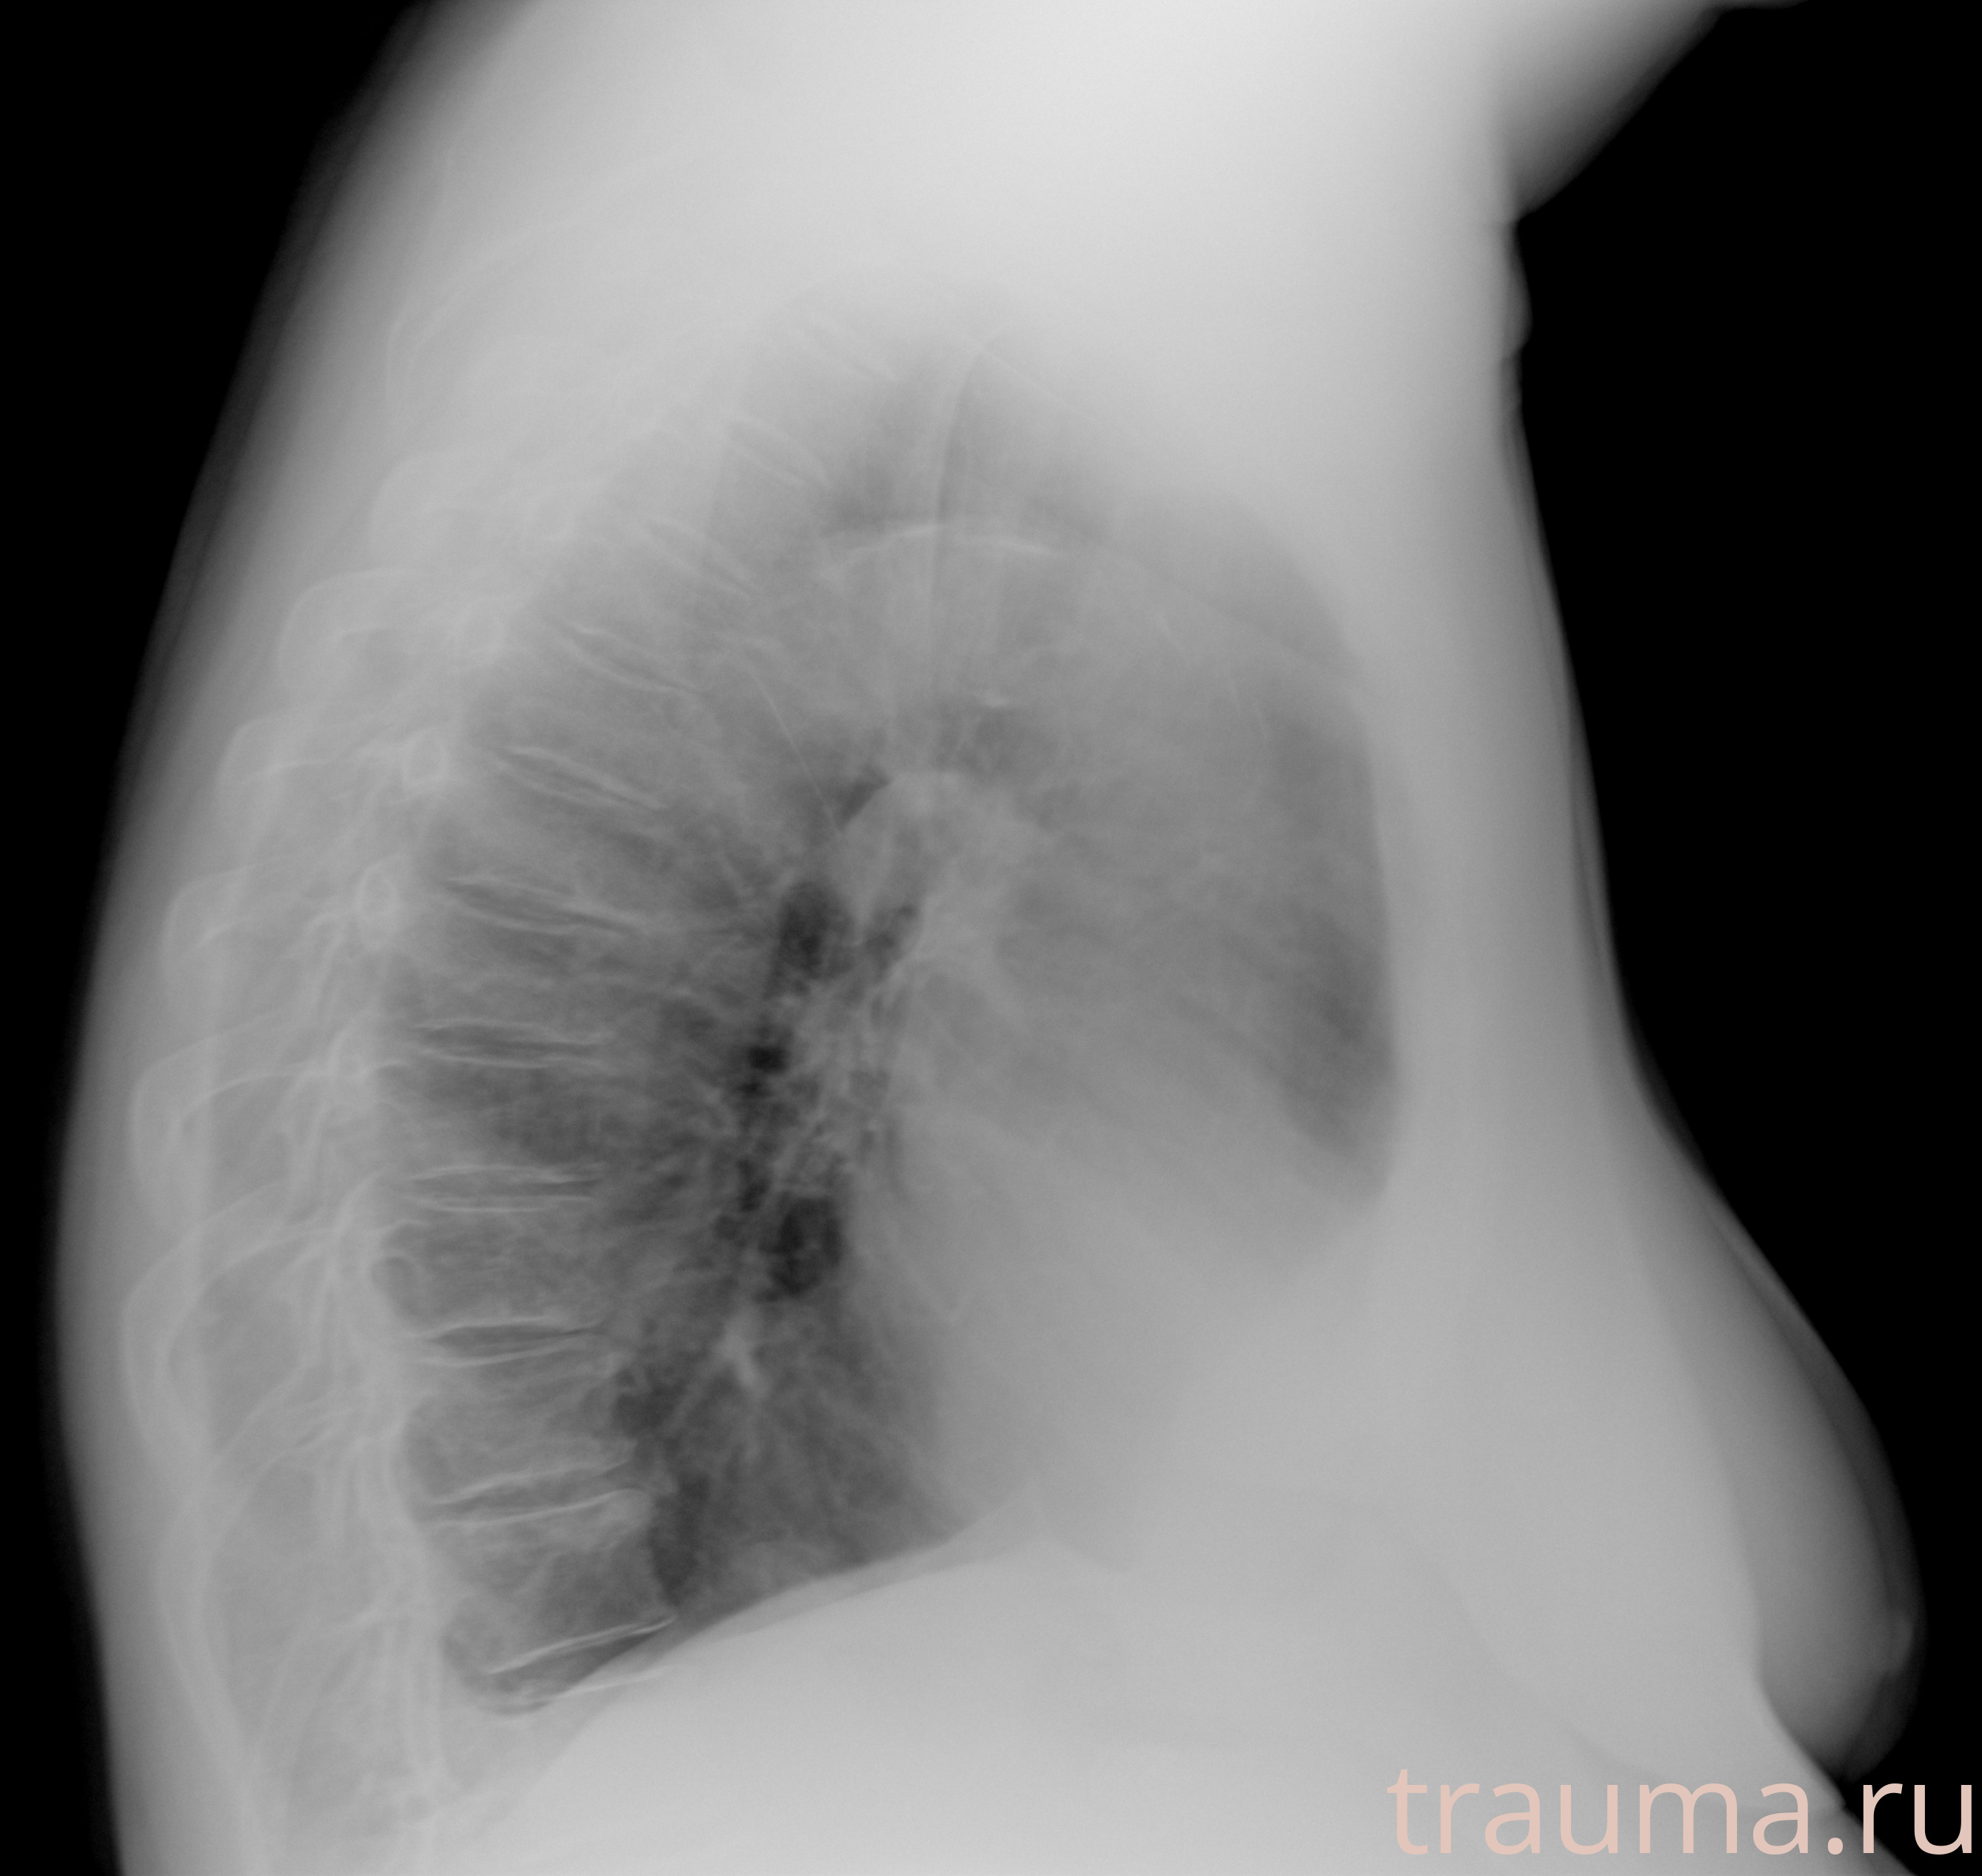

Рентгенограммы

Рентген на дому: по вашему адресу приезжает врач-рентгенолог, травматолог-ортопед с мобильным рентгеновским аппаратом, проводит диагностику травмы или заболевания, делает необходимые рентгенограммы, дает рекомендации по дальнейшему лечению. Получить качественные снимки в домашних условиях возможно благодаря уникальной методике, разработанной МосРентген Центром для института  Склифосовского

при переломе шейки бедра и пневмонии от компании МосРентген Центр - партнера Института имени Склифосовского